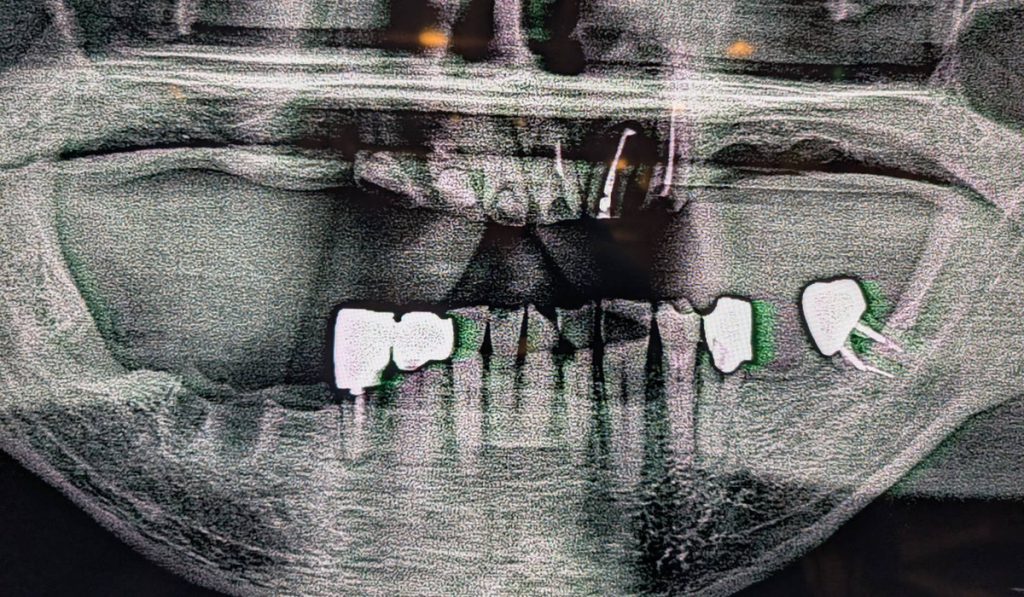

・上顎が総義歯、下顎が両側大臼歯欠損の状態で噛み合わせのバランスが崩れていました。

・30年前に当院を受診された患者様が、歯が無くなり噛めなくなったため再治療を希望されました。

●上の総義歯(入れ歯)を安定させるためには、下の大臼歯部でしっかりと「噛む力」を受け止めなければなりません。

そこで、左右の奥歯にインプラントを埋入し、安定した土台を作る計画を立てました。